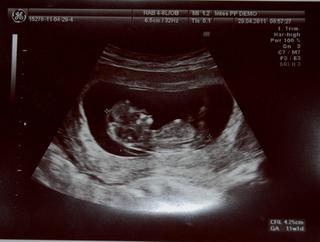

@dominika_sk tvoje spalo a moje dnes skakalo ako besne Dr. vravi, že take čiperne uz dlho nevidela. V kuse machalo rukami a nohami a narabalo zo sebou.... 😀 😀 😀 😀 no uzas.

aj my sme boli vcera na kontole, malinke sa hybalo a schovavalo tvar rucickami, bolo to podarene 🙂

ahojte tak uz som doma.mam magnezium a ascorutin.babatko je ok.bilo mu srdiecko a cumlalo si rucicku.ma 5,32 cm a aj ked som podla pm dnes v 13tt tak podla sona som presne 12tt.nechapem tomu.ale nevadi hlavne ze je vsetko ok.musim lezat s nohami hore , nenamahat sa a ak by som nahodou zacala krvacat okamzite idem lezat do spitalu.